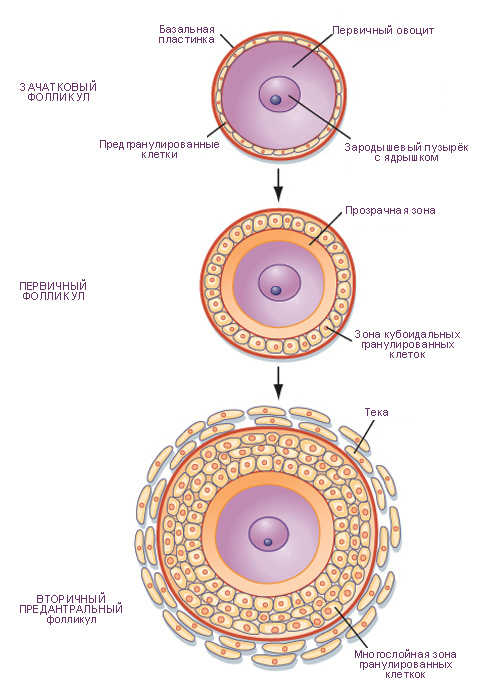

Созревание фолликула в яичнике: этапы и процессы